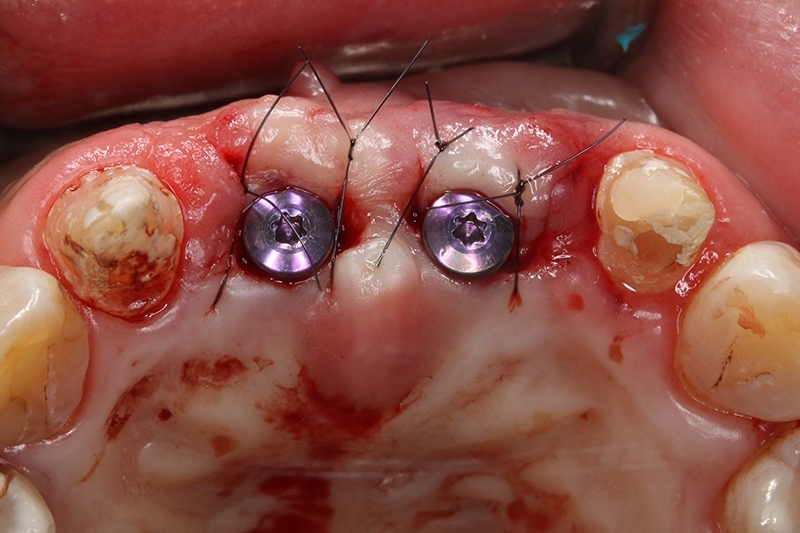

植體植入,置放於理想的水平與垂至高度位置

縫合傷口

等待6個月進行植牙二階手術